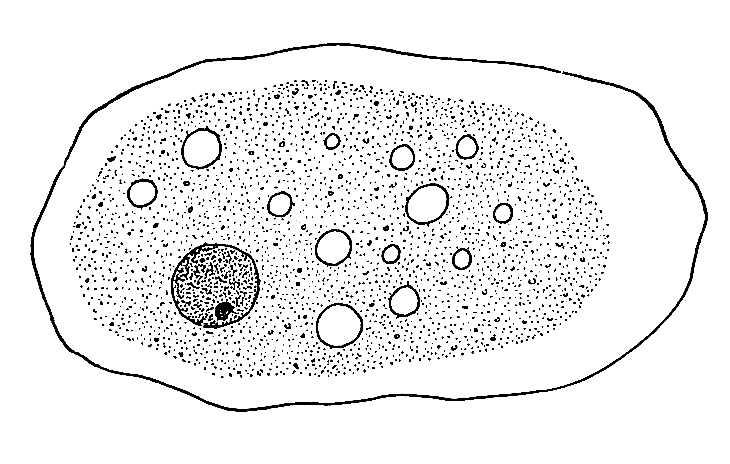

Protozoa- Entoemba histolytica

Protozoa-plasmodium